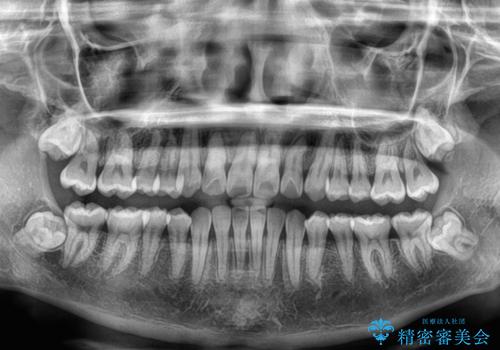

前歯のクロスバイト 裏側に隠れた歯をワイヤー装置で短期間治療

- 上顎前歯のクロスバイトを気にして来院された患者様です。

ワイヤー矯正でもマウスピース矯正でも対応可能でしたが、マウスピースによる自己管理に一切の自信がないとのことで、ワイヤー装置にて矯正治療を行うこととしました。

装置の外見を気にしていましたが、短期間で治療を終えることができるだろうと伝えると、安価であるメタルブラケットを選択されました。

想定通り、1年強で綺麗に仕上げることができました。